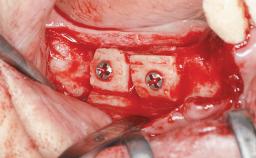

Bone Augmentation Horizontal|Sinus Floor Elevation|Staged|Vertical

Augmentation Materials Autogenous chips|Autogenous block(s)|Xenogenous|Membrane